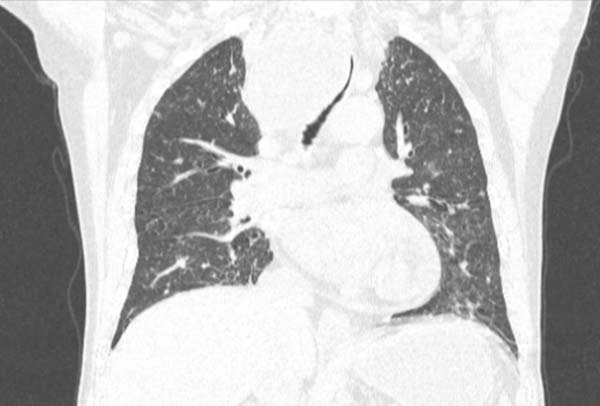

患者张某,因喘息1周入院。1周多前,患者已被明确诊断为食管恶性肿瘤。入院完善CT检查后,结果令人揪心:主气管明显狭窄,且食管肿瘤已压迫并侵犯气管。这是一个极度危险的信号——对于大气道严重狭窄的患者而言,随时面临窒息风险,每一秒的延误都可能意味着生命的终结。

CT、气管镜探查图显食管肿瘤压迫并侵犯气管